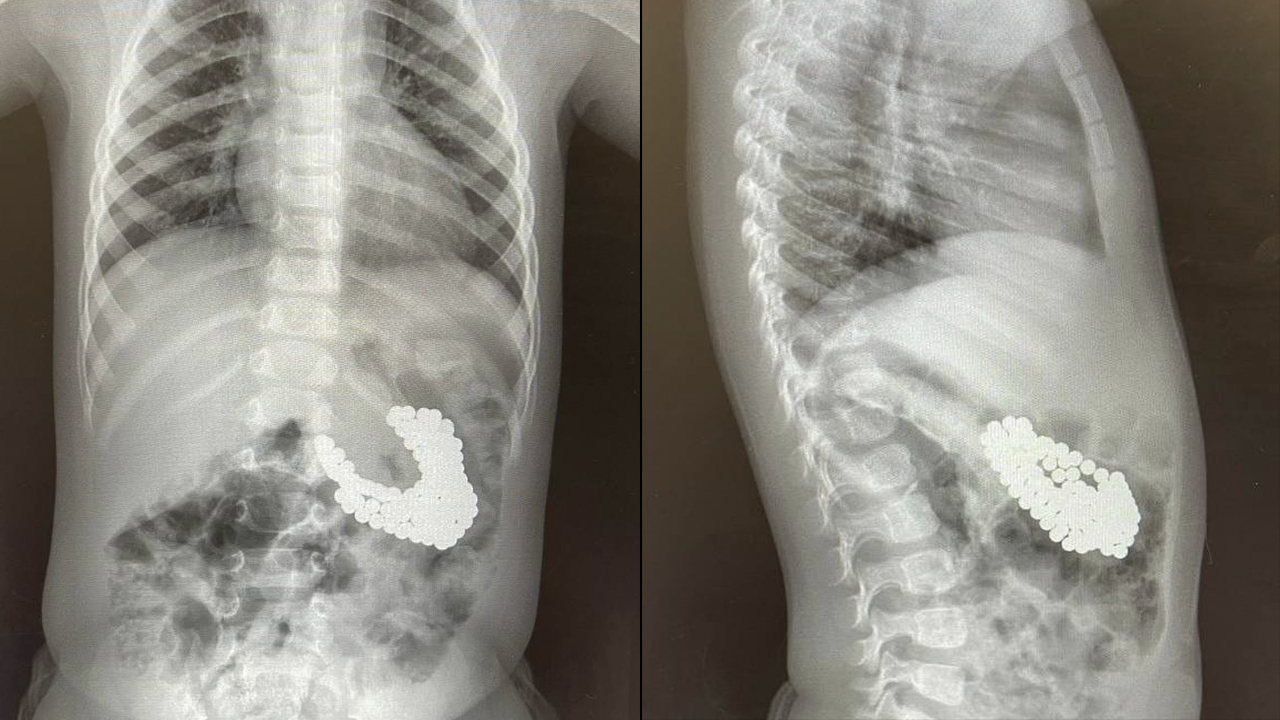

Ребенок съел вату

Ребенок съел вату 111 фотографий